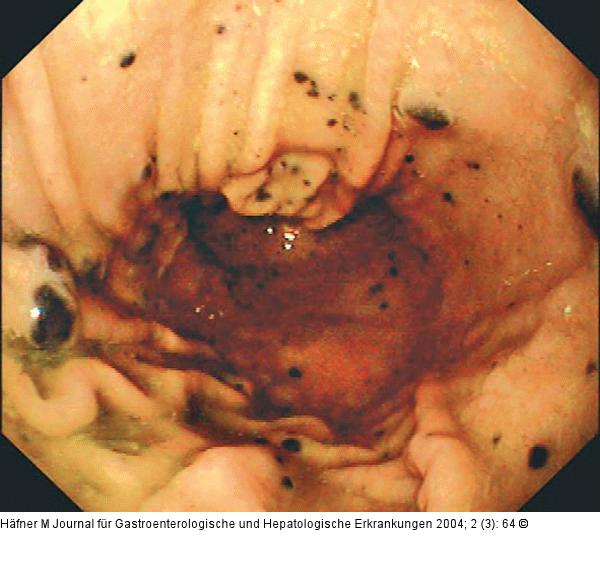

Endoskopie-Bilder-Quiz: Melanom

Journal für Gastroenterologische und Hepatologische Erkrankungen 2004; 2 (3)

: 64

Abbildung 2: Corpus ventriculi